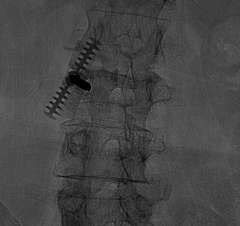

During the procedure, the patient is lightly sedated and lies on their tummy. Under x-ray guidance, we place the needle into the vertebral body (Figure 2). Unlike most pain services where a relatively simple portable C-arm X-ray machine is used, we use the state-of-the-art biplane neuro-angiosuite, which is capable of 3-D navigation in the brain and spine (Figure 3). In rare occasions, placement of the needle is challenging due to previous implantation of metal hardware that obscures the normal bony landmarks, or due to severe osteoporosis. The 3-D navigation capability provides us with the ability to very accurately place the needle without relying on the classic radiological bony landmarks (Figure 4).